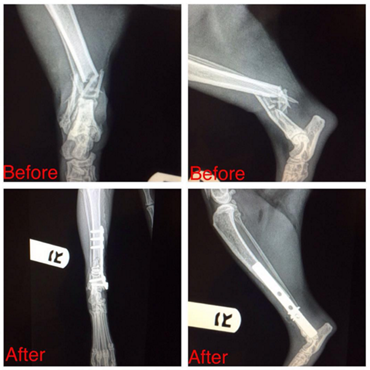

Our team approach to routine and emergency pet orthopedic surgery allows us to provide our patients with quality care that focuses on comfort and safety from start to finish. In treating your pet, we thoroughly investigate every treatment option available. We work closely with specialists and rehabilitation professionals from around the country who support our efforts to ensure that your pet's surgical repair is both safe and effective.

We think outside of the box to find solutions for your pet's successful recovery. We're confident in our team of experienced and compassionate doctors who provide unique, specialized care in feline and canine orthopedics. Our orthopedic veterinary surgeons are leaders in the field of veterinary orthopedics, utilizing advanced technology and approaching each patient from an individual perspective. Through our unique relationship with our talented physical rehabilitation team, our doctors are able to ensure swift recovery times, and overall positive outcomes for our patients.